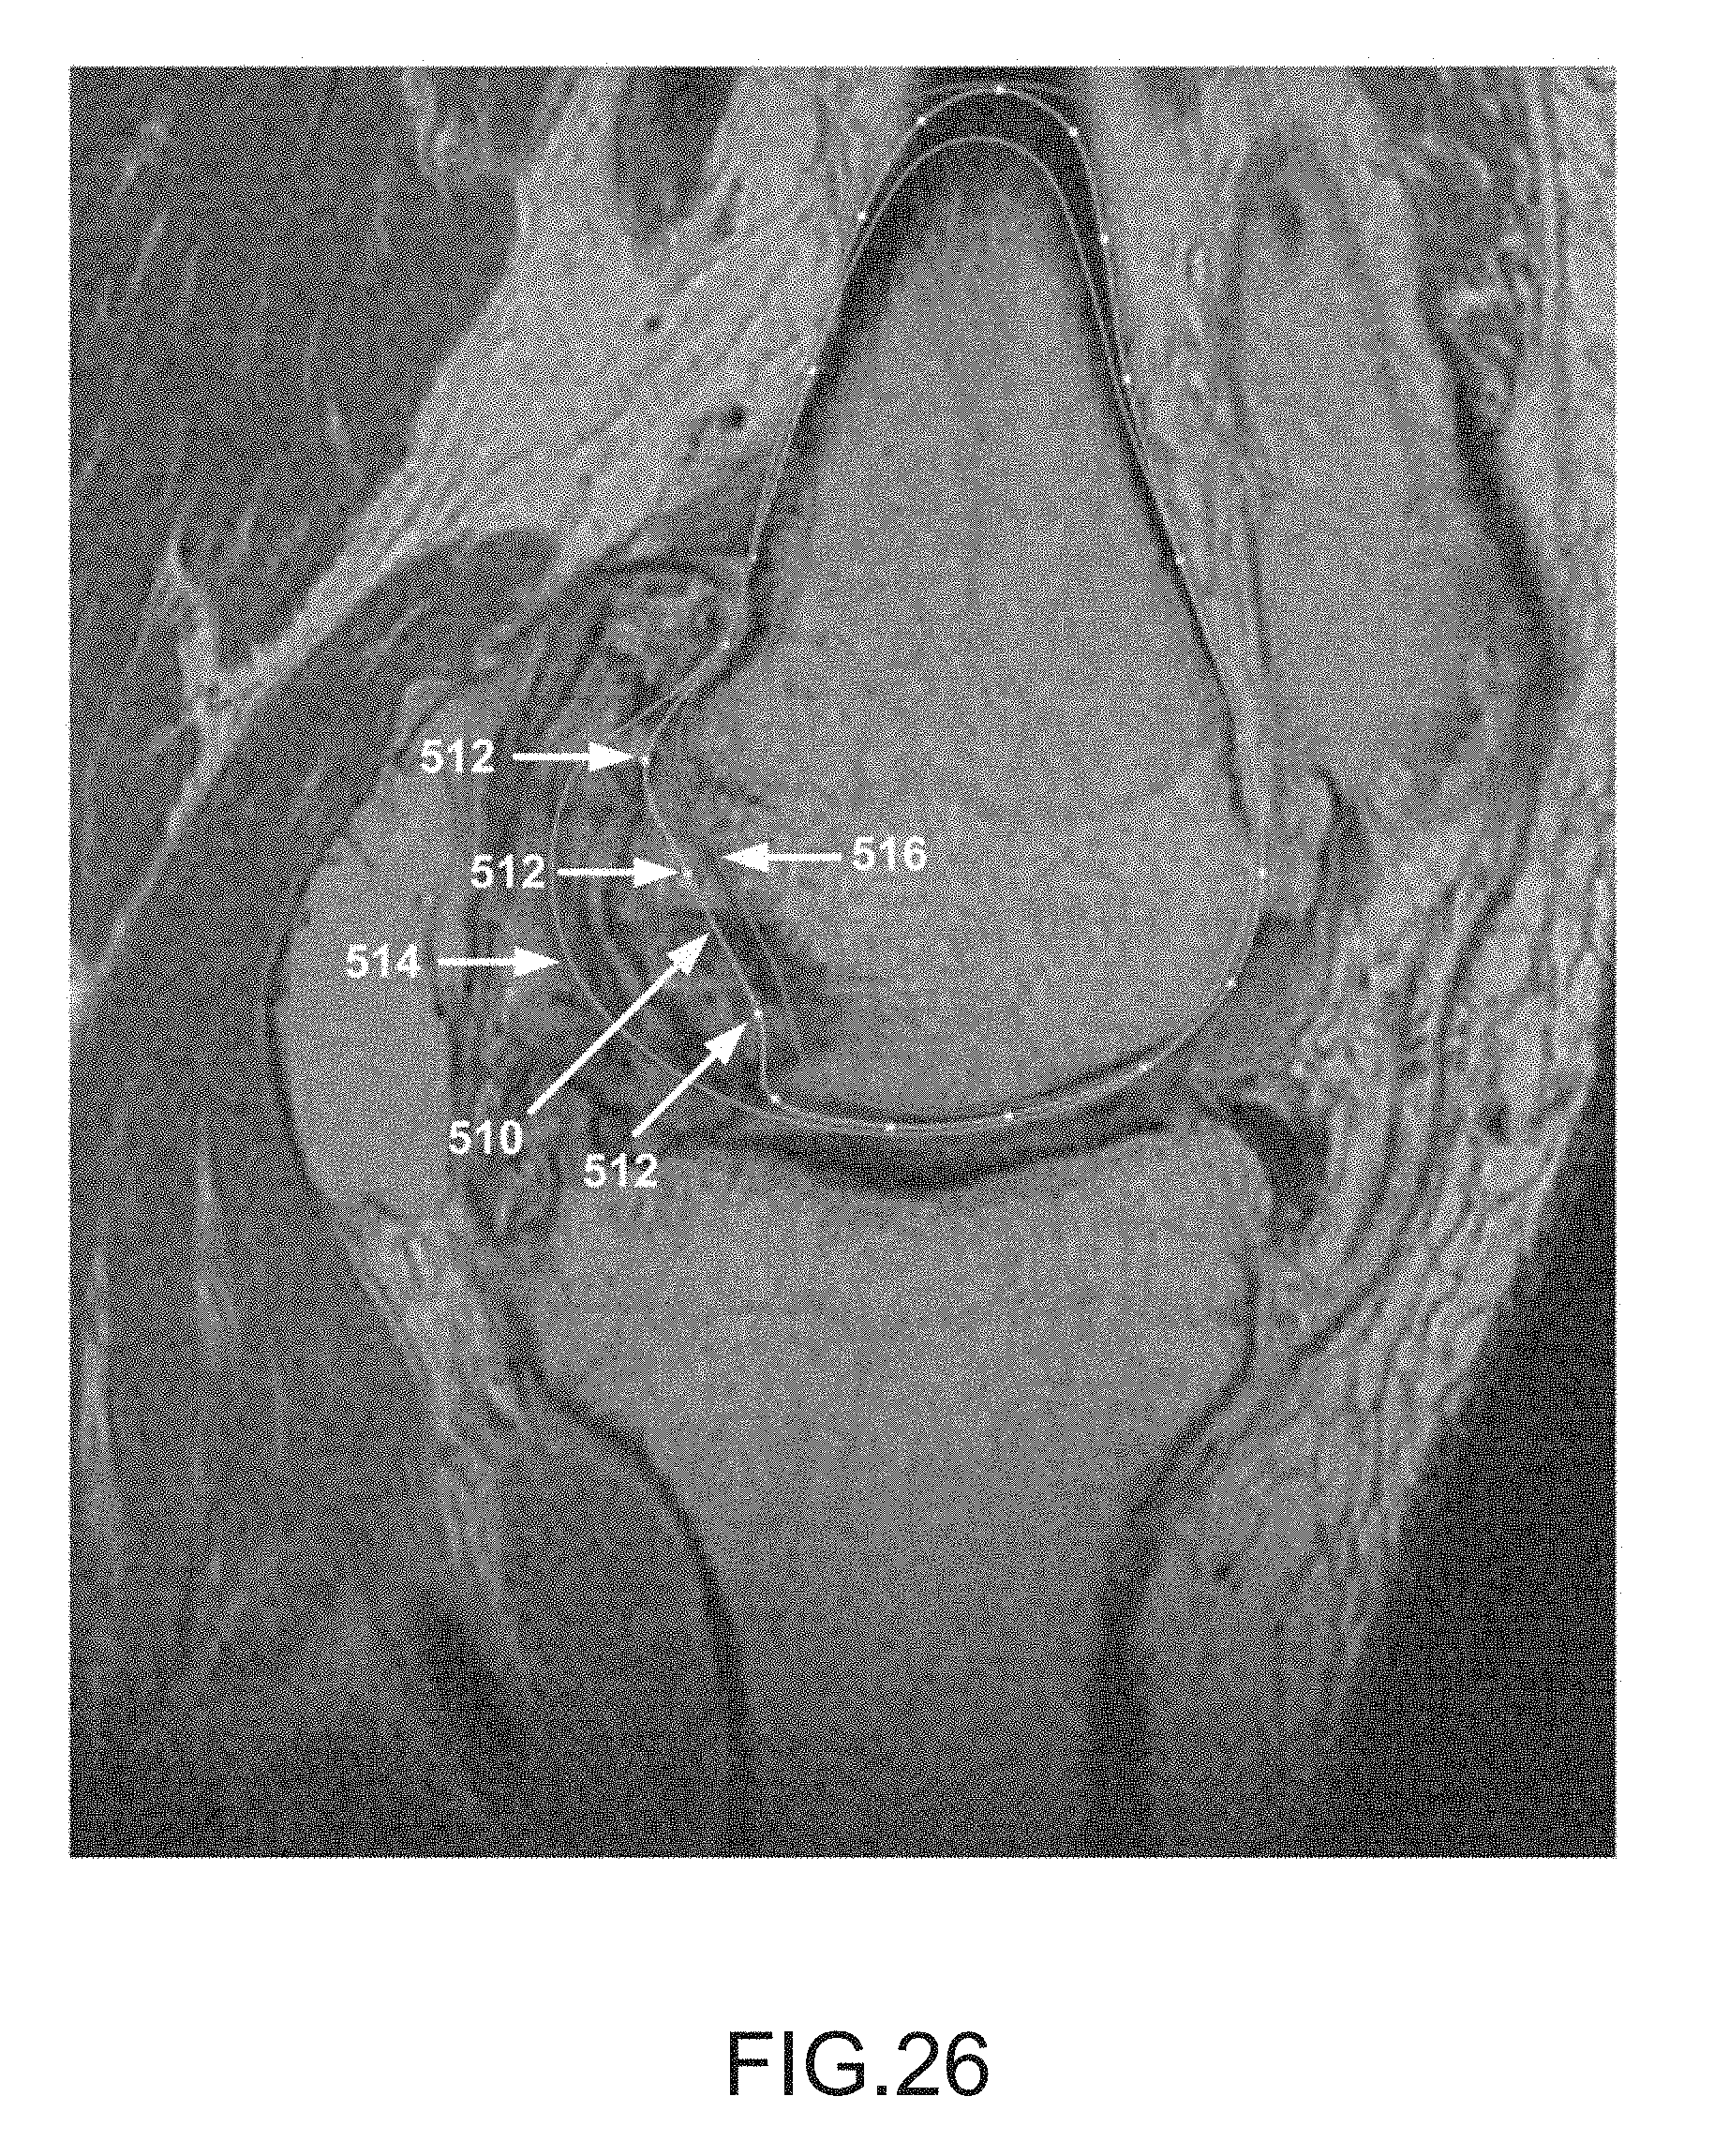

FIG. 26 is a sagittal plane image slice depicting a contour curve with control points outlining a femur with superimposed contour curves of the femur from adjacent image slices.

Typical MRI and CT scan data generally provide images where parts of a bone boundary of interest may be well defined while other parts of the bone boundary may be difficult to determine due to voxel volume averaging, the presence of osteophyte growth, the presence of tissue having similar image intensities in neighboring areas to the object to be segmented, amongst other things. Such poor definition of parts of the bone boundary in the images may cause traditional automated segmentation techniques to fail. For example, FIG. 2A depicts regions 212 within a slice where an object boundary may not be visible due to neighboring tissue having about the same intensity as the feature of interest. Depicted in FIG. 2B are regions 214 that may be extended into the slice from adjacent slices due to a high voxel aspect ratio. Depicted in FIG. 2C is a region 216 of the bone boundary 218 that may disappear or lose regularity when the bone boundary 218 is approximately tangent to the slice.